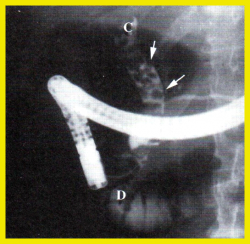

| תצלום 3.8: הרחבת צינור המרה המשותף, בסונר משמאל החיצים מצביעים על צינור המרה המורחב. | |

| תצלום 5.8: EUS - מראה מימין את צינור המרה המשותף בחתך (חץ) ותחתיו את הוריד הפורטלי.

משמאל כיס מרה עם אבן. | |

בדיקת האולטרה-סאונד היא מכשיר עזר חשוב באבחון הלוקים באבנים בכיס המרה, בצהבת או במצבים דלקתיים חריפים. אמינות הבדיקה היא גבוהה - 95%. בבדיקה זו מודגמות האבנים בכיס המרה כנקודות בהירות שמאחוריהן "צל אקוסטי" (Acoustic shadow) - אזור בלא החזרת קול (האבן חוסמת את הקול) (תצלום 1.8). אם הנבדק משנה תנוחה, האבן זזה, והדבר מודגם בבדיקה. אבנים בדרכי המרה ניתנות להדגמה ב- 20% מהמקרים. דרכי מרה מורחבות אפשר להדגים בלוקים בחסימה בדרכי המרה. בחולים אלה ההרחבה יכולה להיות של דרכי המרה החוץ ו\או התוך-כבדיות. (תצלום 2.8 ו- 3.8). נוזל סביב כיס המרה ודופן מעובה של כיס המרה מעידים על דלקת של כיס המרה (תצלום 4.8). אפשר לבצע בדיקת אולטרה-סאונד של דרכי המרה בזמן הניתוח ולאתר אבנים בדרכי המרה.

אולטרה-סאונד אנדוסקופי (EUS): ה-EUS הינה בדיקת US אנדוסקופית המבוצעת דרך אנדוסקופ בסמוך לאיבר הנבדק. גישה זו מאפשרת לראות את אנטומיה ופתולוגיה של דרכי המרה בצורה ברורה. הבדיקה מבוצעת כיום בכל חולה עם הרחבה של דרכי מרה או הפרעה בתפקודי כבד הרומזת לתהליך חסימתי בדרכי המרה (תצלום 5.8).